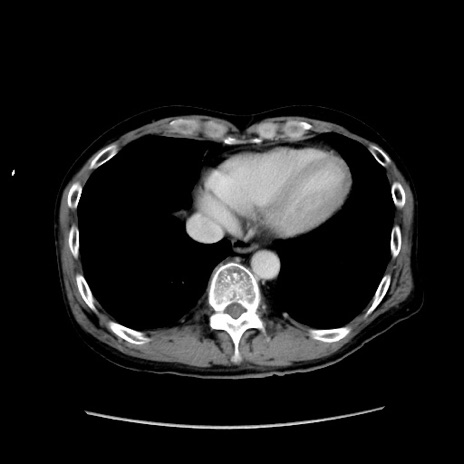

症例37(横断像)

【症例】40歳代 男性

【主訴】腹痛

【現病歴】4時間ほど前に電車に乗車中に臍部上より腹痛出現。徐々に増悪し起立困難となり、救急外来受診。生ものは数日食べていない。今朝お雑煮を食べた。

【身体所見】BT 36.8℃、BP 117/84mmHg、HR 91/min、SpO2 97%、苦悶様、腹部:臍上部広範囲圧痛あり、反跳痛±

【データ】WBC 8100、CRP 0.03